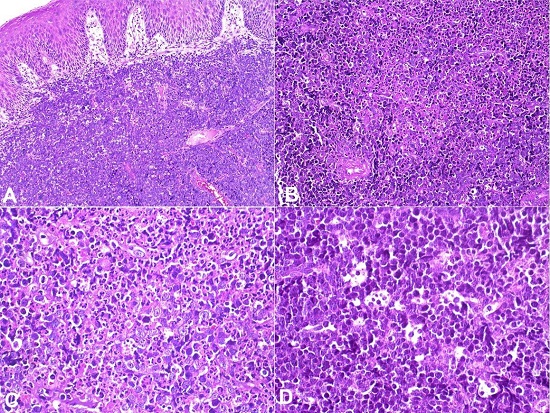

Incisional biopsies were performed in both sides under local anesthesia, and sent for histopathological study. However, after two days of the biopsy, the patient was hospitalized presenting malaise and breathing difficulties. By imaging studies, an abdominal tumor was detected, and patient died within 10 days. Microscopically, the oral lesions revealed a diffuse proliferation of monotonous, medium-sized lymphoid cells with scarce cytoplasm, round basophilic nuclei with fine chromatin, and multiple nucleoli. Nuclear pleomorphism, numerous mitotic and apoptotic figures were common (Figure 2A and B) including tingible body macrophages forming a “starry sky” pattern (Figure 2 C and D). The microscopical diagnosis of high-grade lymphoma was suggested. Immunohistochemistry and in situ hybridization (ISH) for EBV confirmed the diagnosis of SBL.

Immunohistochemically, the tumor was positive for CD20, CD10, Bcl-6, and for EBV-encoded RNA (EBER) by ISH (Figure 3A, 3B, 3C, 4A)¸ and negative for CD3, Bcl-2 (Figure 4B), Vs38c, and MUM-1. Ki67 index was near to 100% (Figure 3D). Based on histological and immunohistochemical findings, the final diagnosis (rendered postmortem) was of SBL.